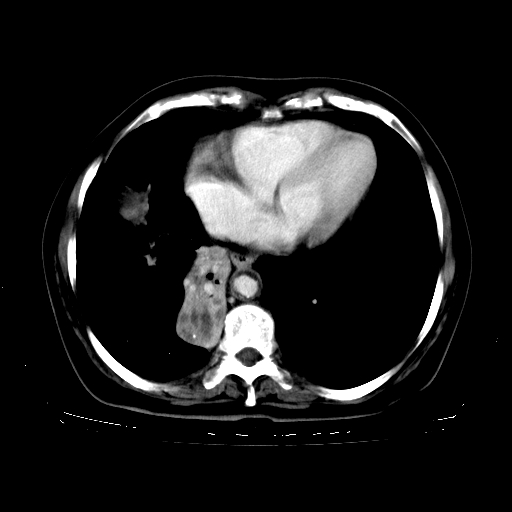

2.胸主动脉夹层。

4、主动脉夹层。

5、右侧少量胸腔积液。

支持,首先一元论解释。胸主动脉部分层面环形低密度,中心强化。环形影不强化。不象真假腔的改变。我考虑动脉炎,不太支持夹层动脉瘤-和大家的观点不一致,希望楼主让患者再做个心血管的彩超吧。